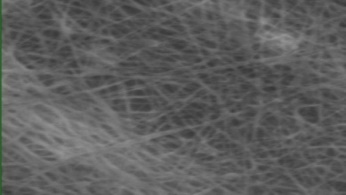

Morphology analysis was adapted from Aytac et al. (2019) [38]. The SEM analysis was conducted to detect electrospun nanofibers' fibre shape and diameter. The electrospun nanofibres from 18 runs were investigated individually by SEM (FEI, quanta 450, Czech). Images revealed the morphology of resultant nanofibers and measured their diameters in nanometres. The average number of records was calculated using a standard deviation estimation. The setting of the SEM machine was conducted on voltage 25.00 kv, magnification 23624 and width (8.3-9.3 mm).

Results of the SEM analysis are listed in table 2, with a wide range of fibre diameters starting from 87.2 nm (run 13) to 2500 nm (run 18). Run 18 did not produce true nanofibers due to the deficient concentration of PVA. The statistical analysis revealed that the effect of each polymer (factor) on the diameter size of the electrospun nanofiber was vast. Therefore, there is a correlation between factors A, B and C and fibre diameter as expressed in equation 5.

Fig. 3: Nanofibres SEM images with nanofiber diameter frequencies. The PVA, PEO and HPMC were symbolised as V, E and P. Data are given in mean±SD, n=3

The morphology of nanofibers would be affected by device parameters such as flow rate, voltage and distance from the collector. Also, nanofibres' properties could be changed due to temperature and humidity. The bead formation appears with a low concentration of PVA (run 2) or a high concentration of PEO and HPMC (runs 6 and 11), as shown in fig. 3. Therefore, increasing PVA concentration leads to beads' disappearance and smooth fibres' formation. Nageeb El-Helaly (2021) and Silva J. A. et al. (2021) reported similar results [47, 48]. Kalluriet al.(2021)[49] studied the relationship between the fibre diameter, bead diameter and flow rate. Thus, they concluded that better fibre uniformity and bead formation were needed at a high flow rate. These results appear clearly in run two and run six and agree with Silva et al.(2021) results [50], who reported that only the concentration of PVA (≥ 15%) could produce uniform nanofibers when using the lower molecular weight of PVA (67,000). Fibre diameter of 15% PVA and more appeared to be in the range 87.11 to 252.5 nm with uniform fibres and disappearance of beads except in run 6, where the beads appear due to increasing the concentration of HPMC as highlighted by Gripet al. (2018) [46].